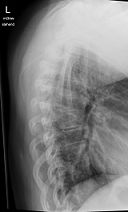

Röntgenbilder

- Dateianhänge

- TSPINE seitlich (oberer Abschnitt)

T bedeutet Top Spine? - TSPINE Bild 2 vk II.png (25.02 KiB) 19770 mal betrachtet

deine Bilder lassen vermuten, dass vielleicht gar nicht die Skoliose dein Problem ist, sondern dein sagittales Profil. (Steht dein Kopf ziemlich nach vorne, wenn du dich vin der Seite betrachtest?) solltest auf jeden Fall einmal zum Spezialisten, im deine Situation kompetent abklären zu lassen. Aus NRW ist wahrscheinlich Dr. Verres in Bingen am nächsten.

mit dem sagittalen Profil meint man das Profil von der Seite gesehen. Laut deinen Aufnahmen hast du eher eine geringe Skoliose, aber einen ziemlichen Rundrücken und Hohlkreuz was auch Beschwerden machen kann und das die Ärzte auch gerne übersehen oder nicht sehen wollen. Deshalb ist es auch wichtig, einen Spezialisten aufzusuchen, der dies auch mit behandeln kann. Leider ist dies keine Ganzaufnahme, dann würde man das eher sehen. Es gibt hier schon genug Berichte, die das mit Hyperkyphose und -lordose gut beschreiben. Also lesen bildet...

Dem kann ich mich nur anschliessen, es sieht sehr nach Rundrücken (Bild 2-Hyperkyphose) und Hohlkreuz (Bild 1-Hyperlordose) aus.sloopy hat geschrieben:deine Bilder lassen vermuten, dass vielleicht gar nicht die Skoliose dein Problem ist, sondern dein sagittales Profil.

Deine Brustwirbelsäule macht aber, jetzt nachdem ich nochmal hingeschaut habe, tatsächlich den Eindruck, als würdest du eine Hyperkyphose haben und dein Kopf sich nach vorne legt, zumindest wenn ich deine Halswirbelsäule, auf dem Bild und in meiner Phantasie, weiter zeichne.